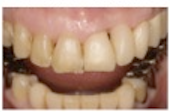

初診時(2003年12月)

最終補綴物装着時(2007年9月)

最終補綴物装着12年経過時(2019年1月)